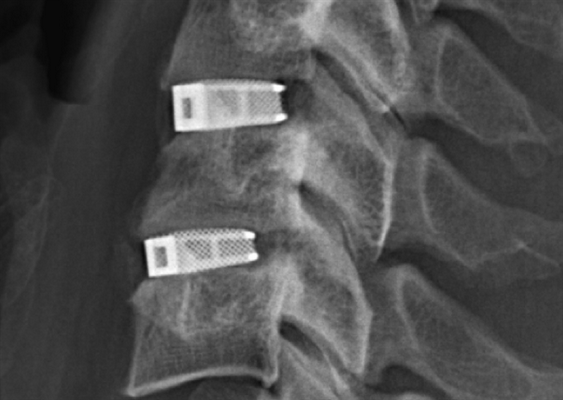

• специальные приспособления, из которых чаще всего используются кейджи.

Кейдж имеет форму полого цилиндра, наружная поверхность снабжена винтовой резьбой, которая облегчает введение его в межпозвоночное пространство и предупреждает самопроизвольное выпадение. Отверстия, сделанные в стенках, позволяют спонгиозному материалу, заполняющему кейдж, прорастать в прилегающие тела позвонков.

Они выпускаются различных размеров, форм, изготавливаются из разных материалов (чаще всего из титанового сплава). Предварительный подбор кейджей для конкретного больного производится индивидуально перед операцией на основании выполненных спондилограмм, а также данных компьютерной и магнитнорезонансной томографии. Окончательно этот вопрос решается во время операции, после уточнения размеров межпозвоночного диска.

Кейджи, вводимые в межпозвоночное пространство, предупреждают его сдавление, придают послеоперационную стабильность данному двигательному сегменту, фиксируют необходимое расстояние между телами позвонков.

Кейджы межпозвоночных дисков поясничного отдела.